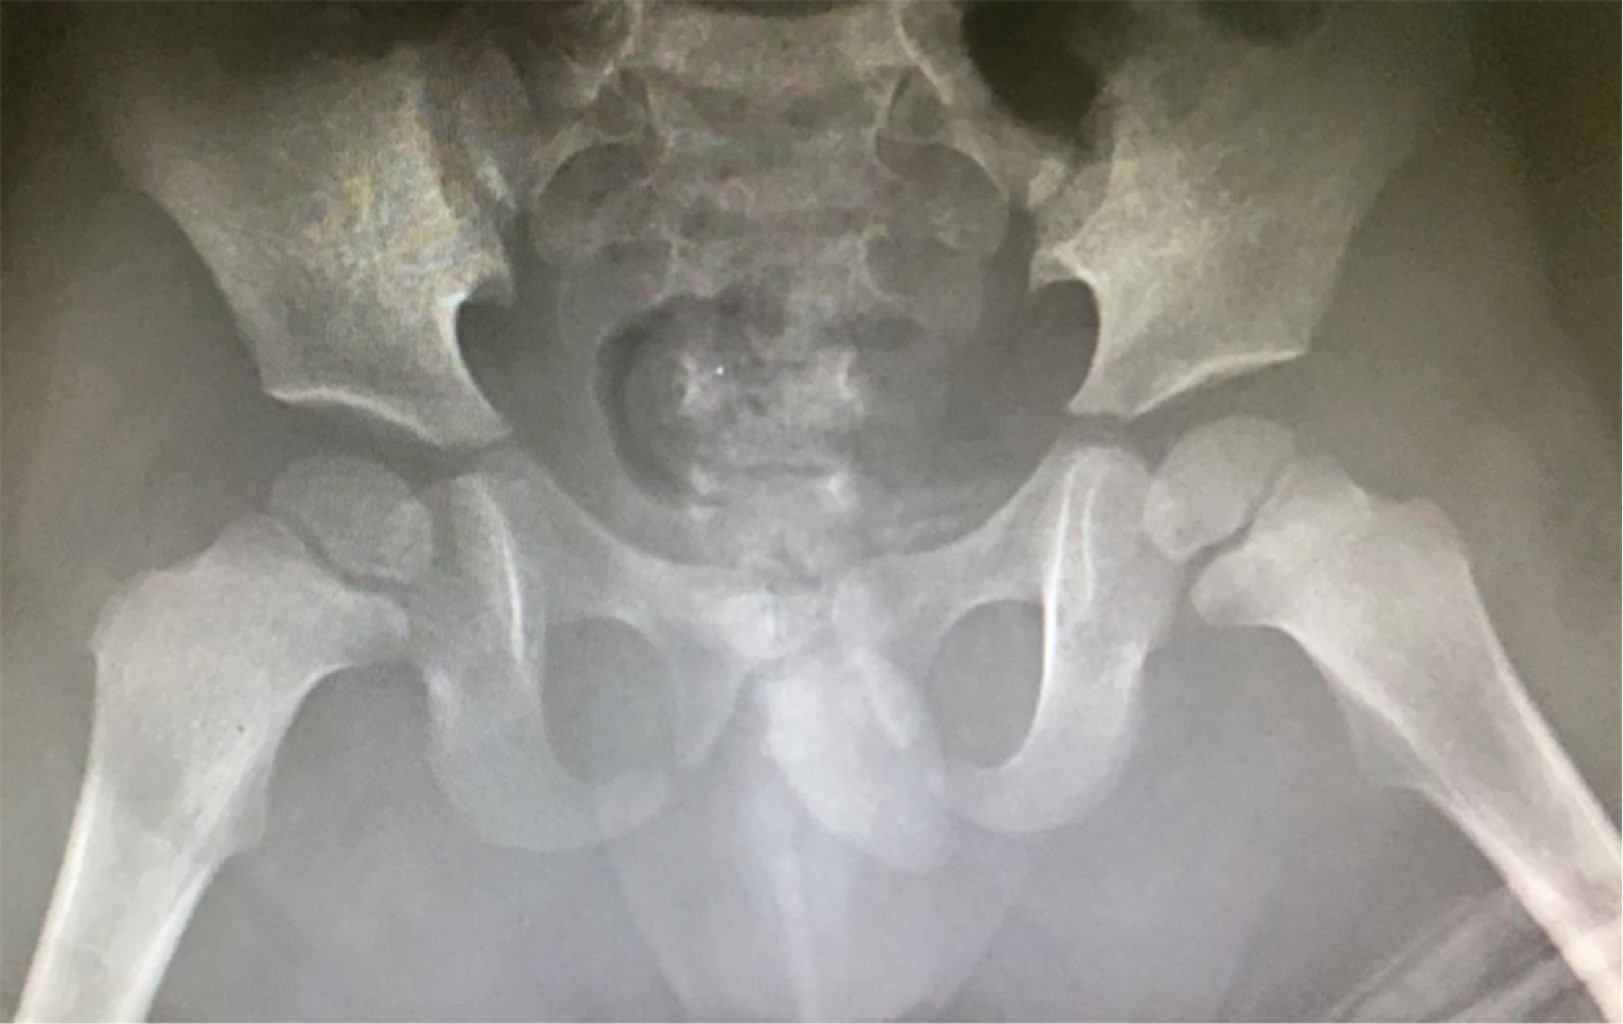

Traumatic anterior hip dislocation in children: a case report

Traumatic anterior dislocation of the hip is uncommon in children, and may result from low energy trauma. Treatment, like all traumatic dislocations, is an emergency. We present the case of a two-year-old boy with traumatic anterior hip dislocation following a fall. Importance: There is little support in the literature for traumatic anterior dislocation of the hip in children due to low energy trauma.

2020     |     www.medigraphic.com